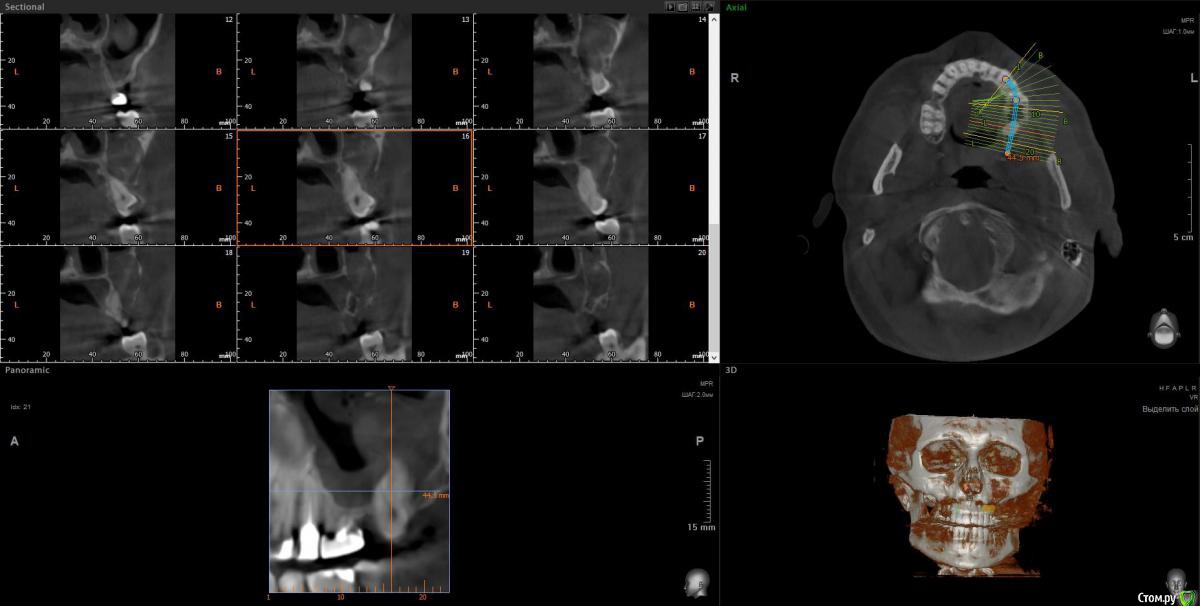

wladdX Опубликовано 5 марта, 2019 Поделиться Опубликовано 5 марта, 2019 Корональная проекция Сагиттальная справа Сагиттальная слева 16 26 28 Ссылка на комментарий

kramer Опубликовано 5 марта, 2019 Поделиться Опубликовано 5 марта, 2019 В общем скачал я КТ. Что касается зуба 26, да, там есть признаки воспаления вокруг корней, лечить / удалять зависит от состояния тканей зуба и возможностей врача. Но лично мне не кажется, что этот зуб играет главную роль в возникшем гайморите. Обратите внимание, в области 8 зуба (см. срез) внутри пазухи есть некий очаг, содержащий неоднородные по плотности элементы (более светлые включения, а выше пузырьки воздуха). Снимок не особо четкий, но такое ощущение, что в области 8 зуба вообще нарушена целостность боковой стенки пазухи. Кроме того, с правой стороны все зубы в порядке, а явления гайморита тоже имеются (там вообще почти вся пазуха забита). Соустья с носом закрыты. В общем, в данной ситуации я бы более детально обследовал 8 зуб, если там все нормально, то пусть ЛОРы эндоскопически лезут в пазухи и убирают это все. Ссылка на комментарий

kramer Опубликовано 5 марта, 2019 Поделиться Опубликовано 5 марта, 2019 Я предлагаю вам такой алгоритм действий. 1. Вы идёте к терапевту, который сможет оценить шансы на перелечивание каналов в зубы 26. Если можно, перелечиваете, если нет, то см. п.2. 2. Вы идёте к хирургу, который должен определить, нужно ли удалять 28 (я бы удалил). Зуб удаляется, всё, что можно вычистить через лунку, промывается, вычищается. Скорее всего будет перфорация в пазуху, по возможности её надо будет устранить. Соответственно, если заранее будет известно, что 26 лечению не подлежит, удалить его тоже. 3. Через 3-4 месяца повторить КТ и с чистой совестью идти к ЛОРам, тк одонтогенных очагов не осталось. Выполнить двустороннюю эндоскопическую синусотомию 4. В случае удаления 26 на предыдущих этапах, подумать о том, как его возместить Ссылка на комментарий